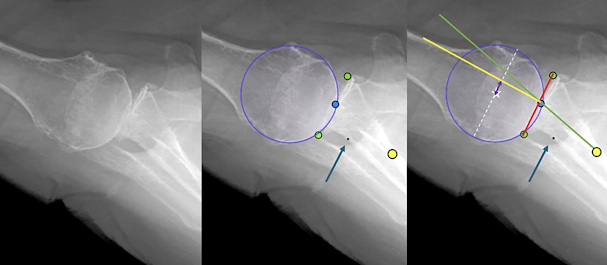

A recent study, Can computer vision / artificial intelligence locate key reference points and make clinically relevant measurements on axillary radiographs? demonstrated the potential of artificial intelligence in assessing clinically important relationships on standardized axillary x-rays. Standardized pre and post arthroplasty axillary radiographs were manually annotated by shoulder surgeons locating six reference points as shown the figure below:

The anterior and posterior edges of the glenoid face are indicated by the green dots.

The center of the glenoid face by the blue dot.

The base of the glenoid vault by the yellow dot.

The spinoglenoid notch by black dot at tip of arrow.

The circle fitting the humerus articular surface by the blue circle.

These points were then used to measure glenoid version and humeroglenoid alignment (HGA-AP). Version was measured as the angle between the red and green lines. HGA-AP was measured as the perpendicular distance (double headed arrow) between the centre of the circle (star) and the perpendicular bisector (yellow line) of the glenoid face line (red line) divided by the diameter of the circle (dotted white line)